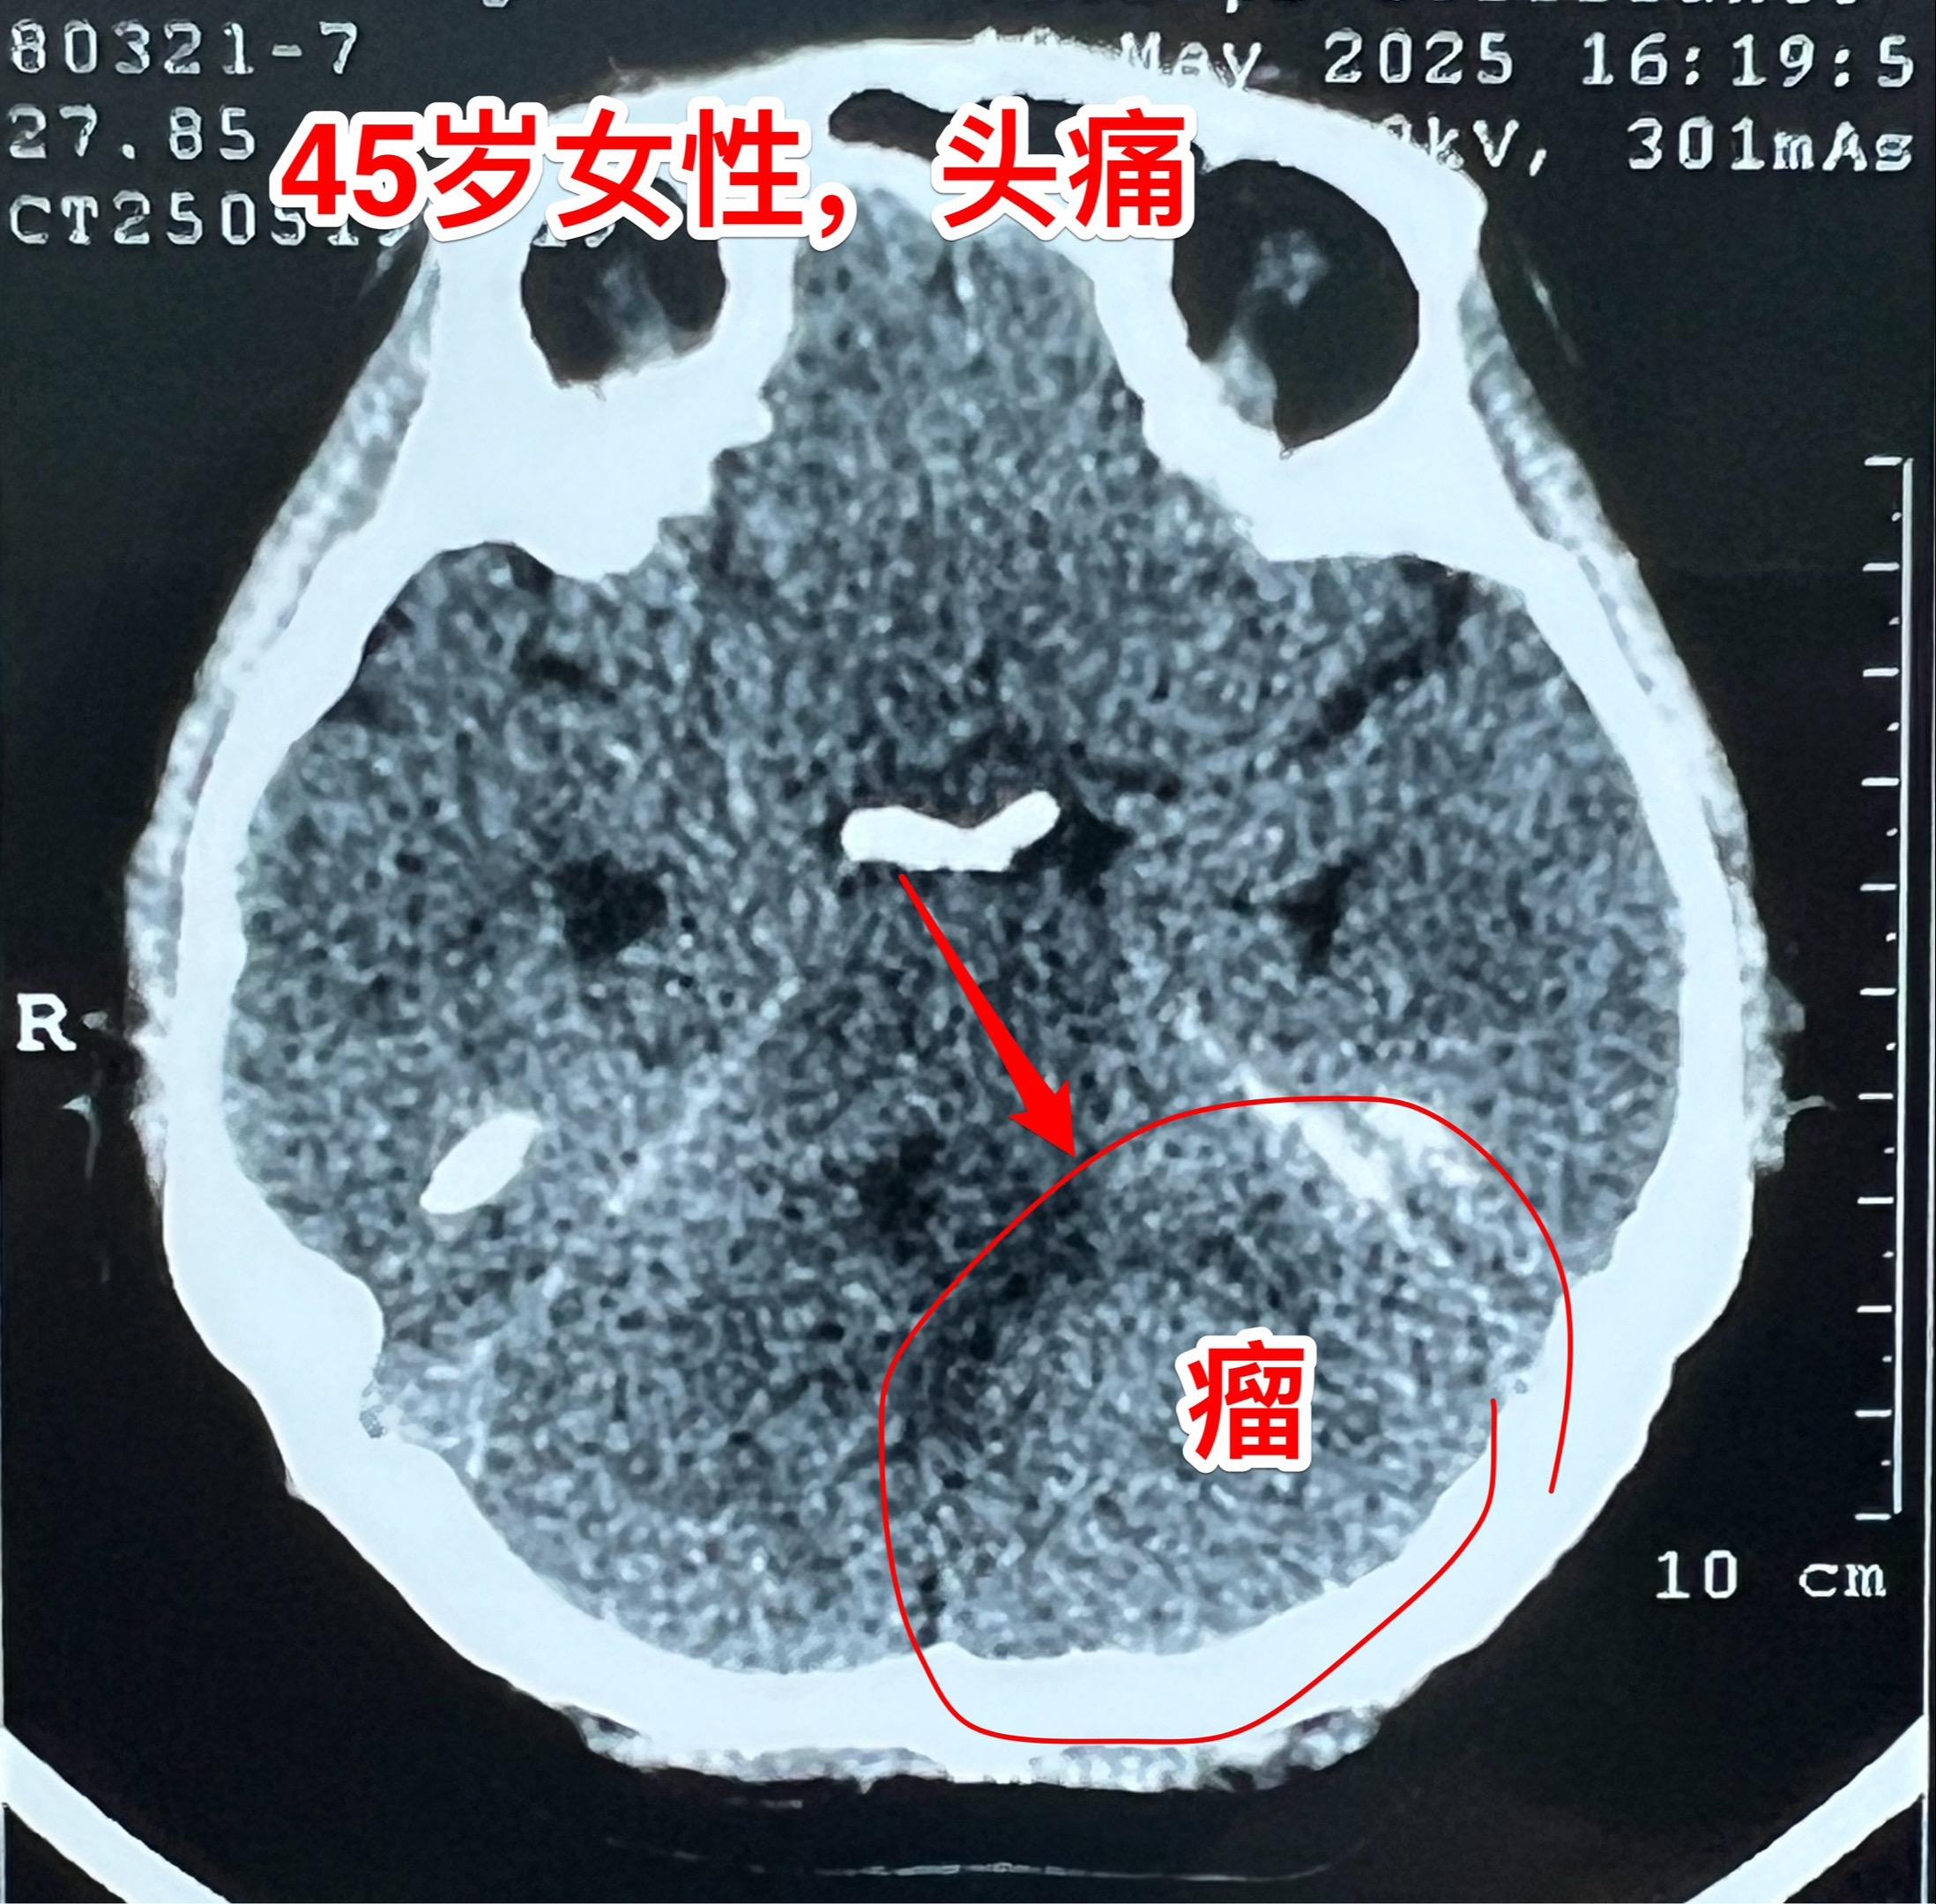

45岁女性因头痛发现脑膜瘤。45岁呼伦贝尔女性,在北京工作。头痛症状不剧烈,无呕吐。到医院就医,作头部CT检查发现可疑问题,再作磁共振检查发现左侧小脑表面有个巨大的脑膜瘤,伴有脑积水。 5月23日作了手术(只能是开颅手术)将脑膜瘤完全切除。 这样的脑膜瘤属于相对浅表位置的肿瘤,比颅咽管瘤手术要容易的多。脑膜瘤虽然是良性肿瘤,也有一定的复发率。